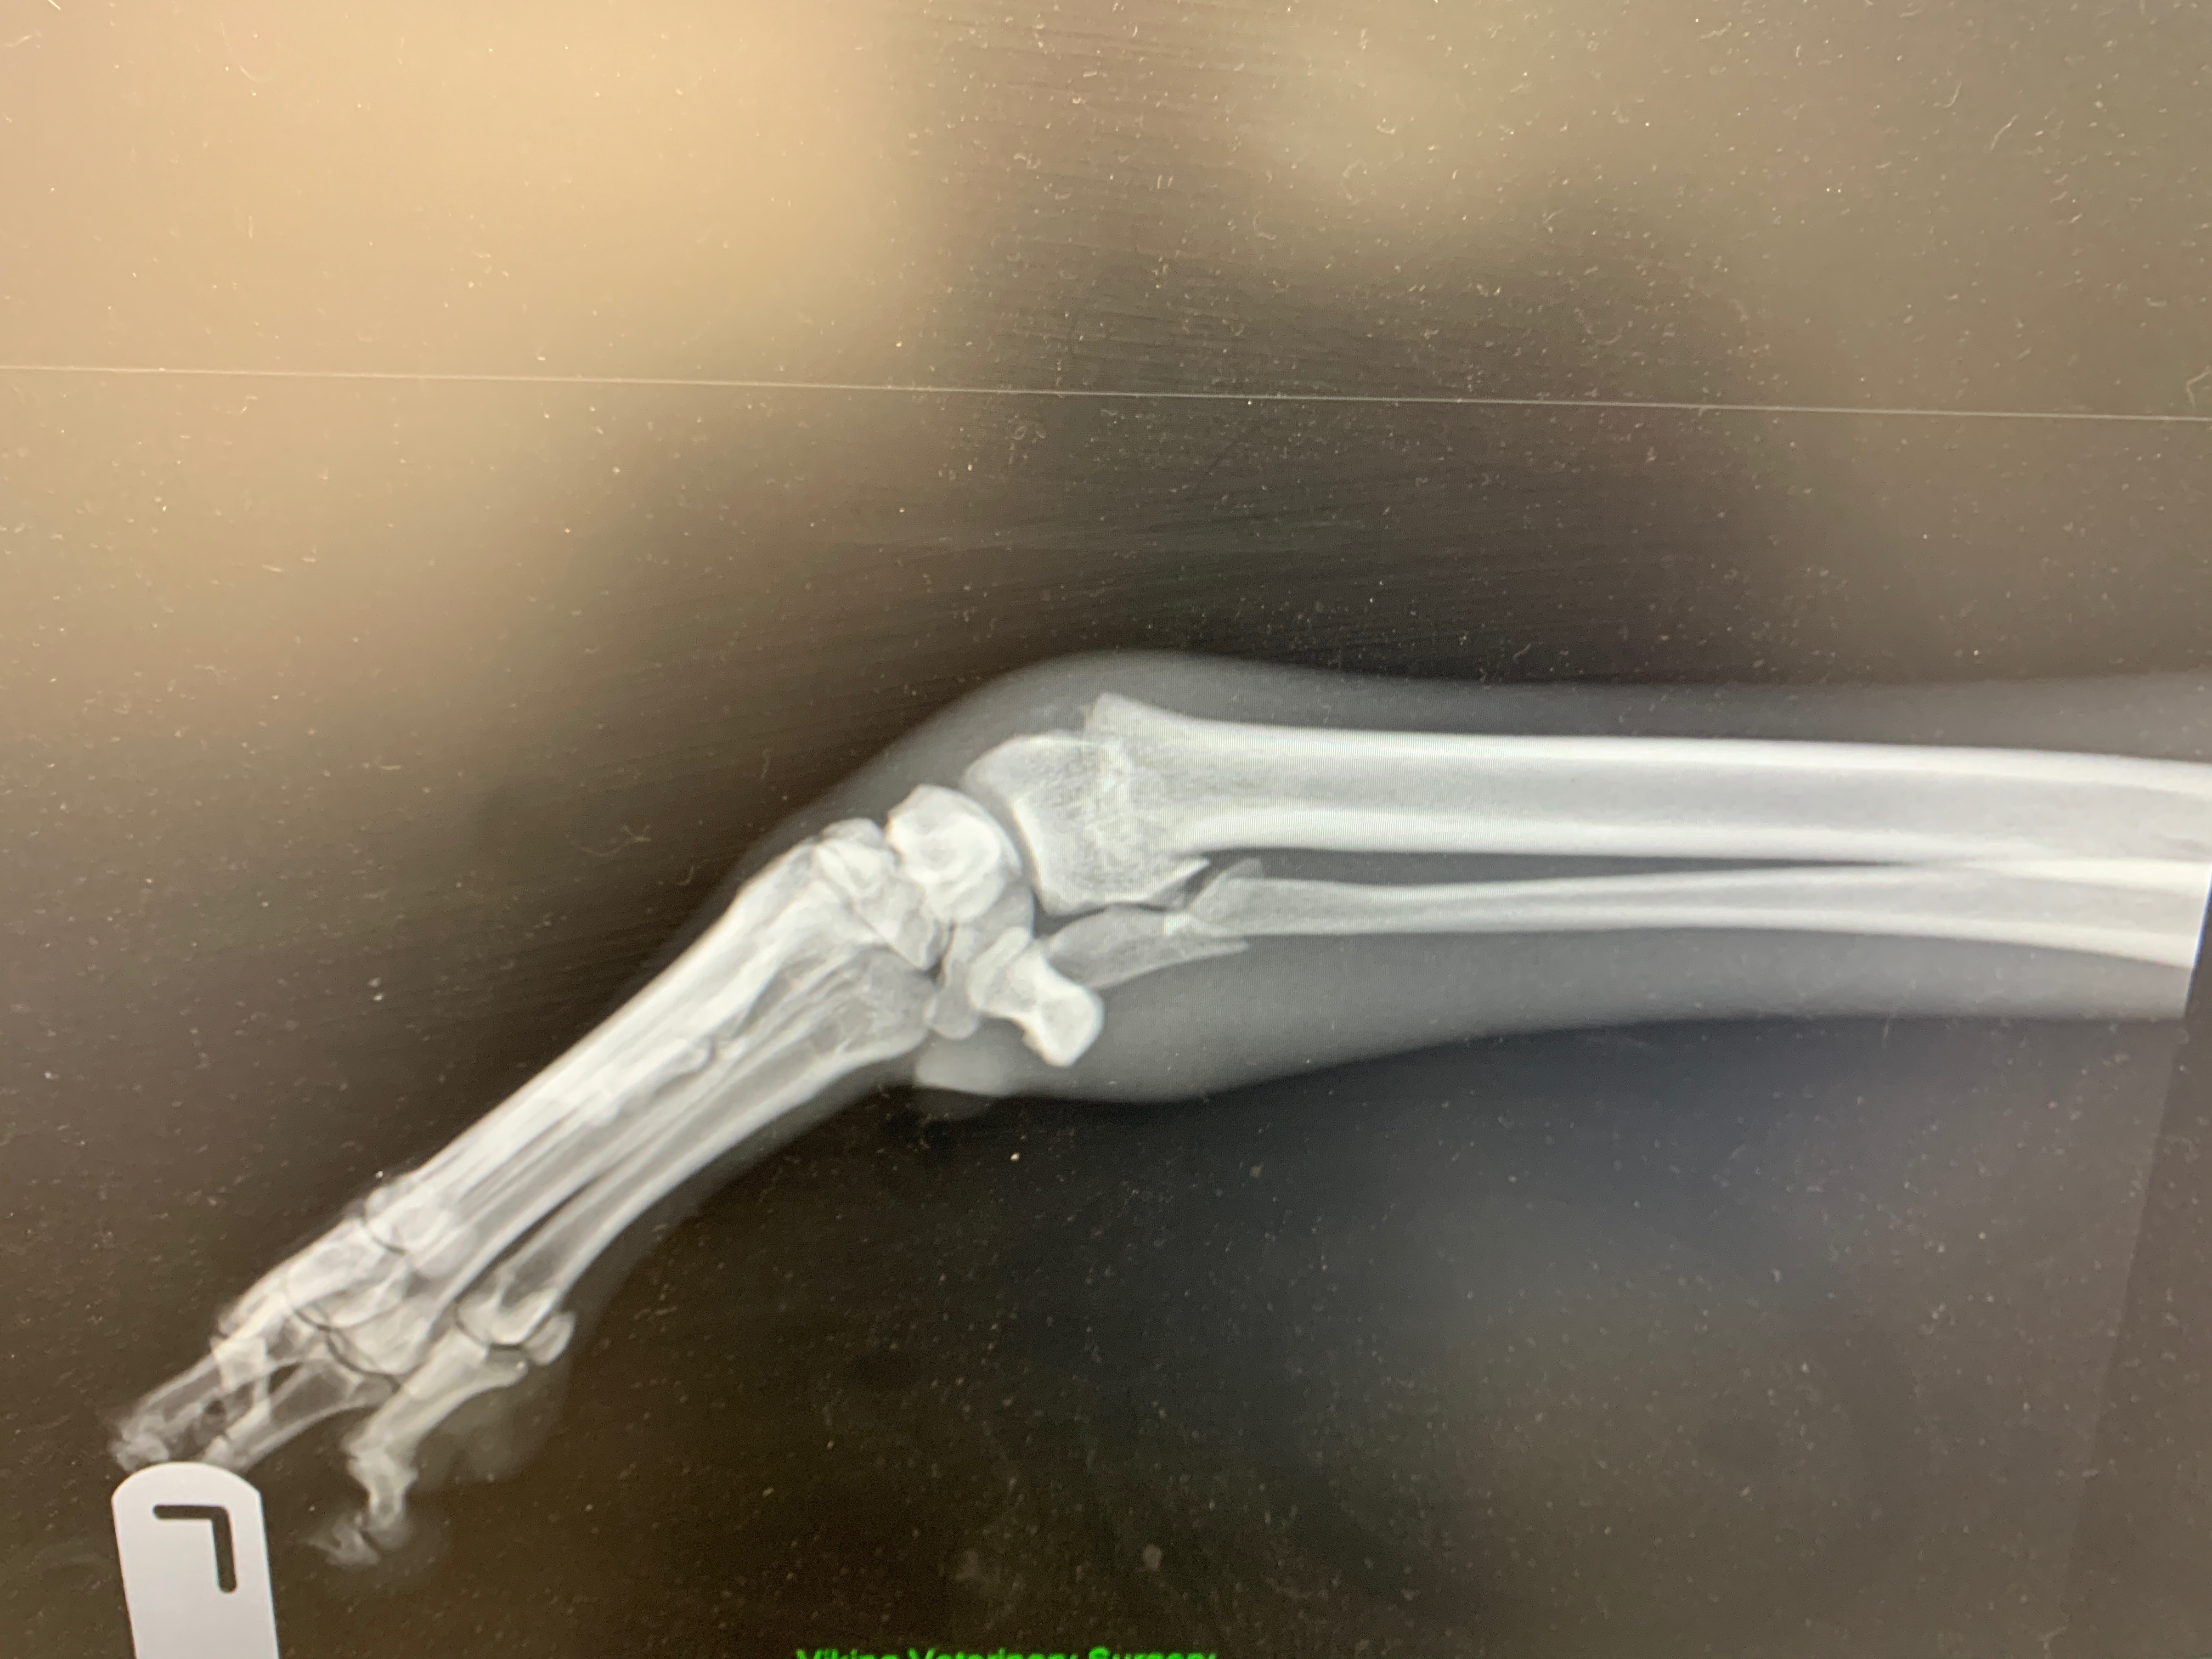

Jess has been in foster with me since she was found on December 9th with a badly broken leg. We tried treating conservatively with a cast but unfortunately she has developed painful pressure sores and casting is no longer an option.

Jess’ best chance at recovery is referral surgery at Blackpool where we have been quoted €2500 - funds I unfortunately do not have.